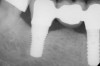

Figure 3   Radiographic appearance of the repaired osseous defect seen in Figure 2 approximately 6 months after extraction and immediate bone grafting of the socket. Note the radiographic repair of the bone on teeth Nos. 4 and 6.

Figure 3

Figure 4  Clinical photograph showing preservation of the ridge seen in Figure 3.

Figure 4

To meet the needs of the new paradigm, treatment techniques have evolved for bone preservation. Figure 1 shows a case in which tooth No. 5 had advanced bone loss and the treatment option was to save it. The patient did not opt to have this treated, however. Figure 2 shows the same area approximately 18 months later when the advanced bone loss was also affecting the adjacent teeth. Traditional treatment—extraction of this tooth—would have led to a significant hard- and soft-tissue defect. Use of the alternative treatment—grafting of the socket at the time of extraction19,20—preserved the hard and soft tissue (Figure 3 and Figure 4). Grafting the socket to minimize postextraction ridge shrinkage is a much more conservative approach than performing ridge augmentation after extraction,21 which would have been required if the socket grafting had not been done in conjunction with the extraction.